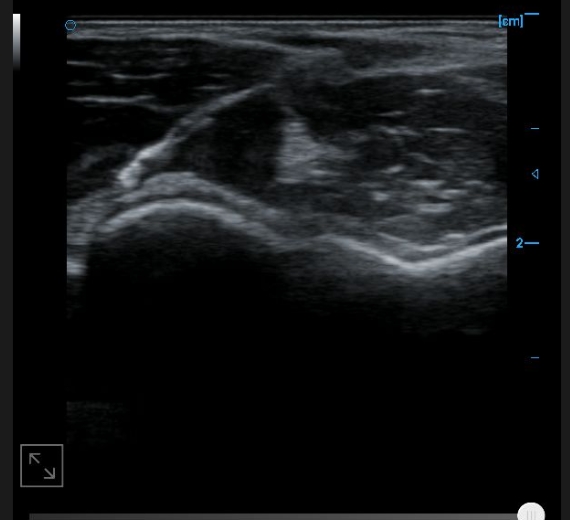

Image of plantar aponeurosis B

B image of toe and flexor digitorum tendon

B-image of the anterior cross-section of the upper arm

Cross sectional B-image of the distal tendon of the biceps brachii muscle

B-axis imaging of the distal tendon of the biceps brachii muscle